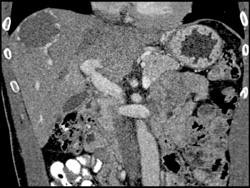

Patchy Liver Enhancement Due to Portal Vein Thrombosis (PVT)